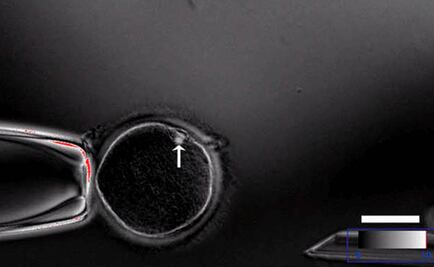

Han encontrado secuencias de ADN específicas del virus